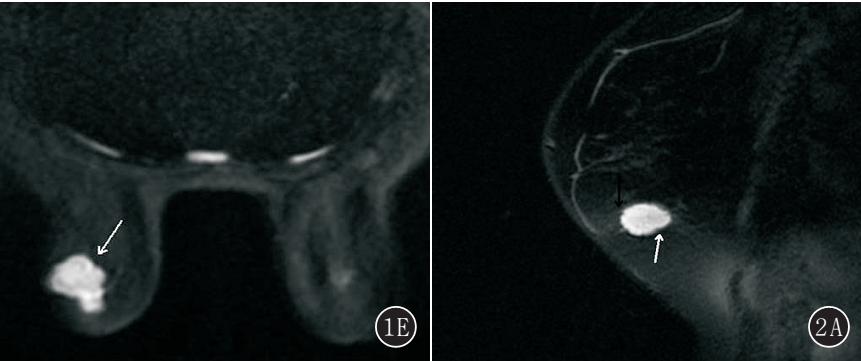

图2A~E 女,54 岁,右侧乳腺单纯型黏液腺癌。 A. T2 WI 右侧乳腺外下象限卵圆形肿块(白箭头),明显高信号,边缘多发细毛刺(黑箭头);B. T1 WI 平扫呈周边环形等信号,中心不均匀低信号(白箭头),边缘多发细毛刺(黑箭头);C. 动态增强呈环形强化(白箭头),强化环厚度不均匀,边缘多发细毛刺(黑箭头);D. 时间-信号强度曲线呈持续型;E. DWI 呈明显高信号(白箭头)